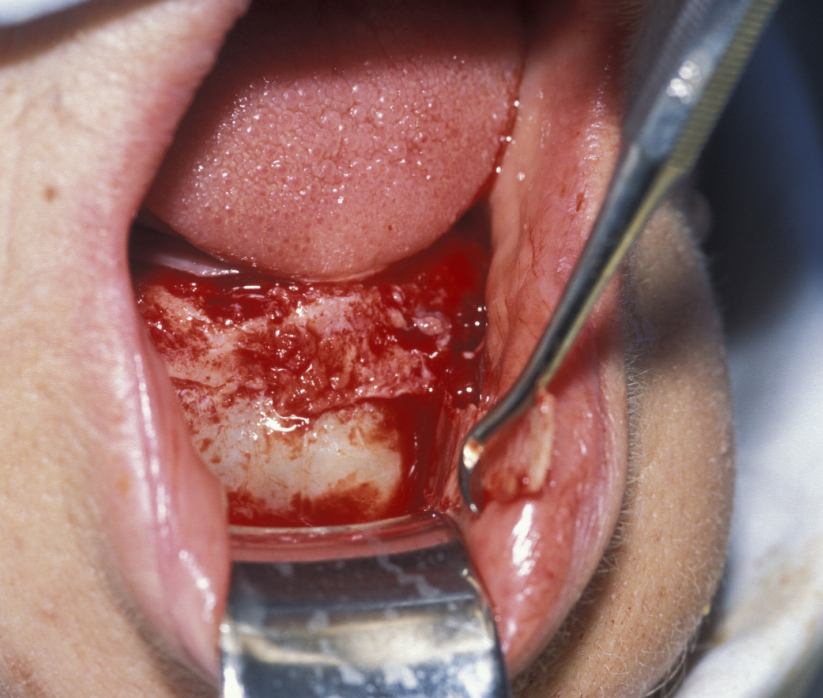

Large cysts in which enucleation may result in extensive local damage or patients who are unfit for more extensive surgery can be managed by marsupialization. This involves exposing the cyst lining and removing a small window from the lining. This is then sutured to the mucosa. The cavity can then be packed with an antiseptic dressing and regularly changed as the cavity heals from underneath. A step by step illustration of the procedure is shown in Figures 7 to 9.

Figure 9: The defect is packed with iodoform gauze. This allows gradual resolution of the defect as new bone displaces the cavity lining.